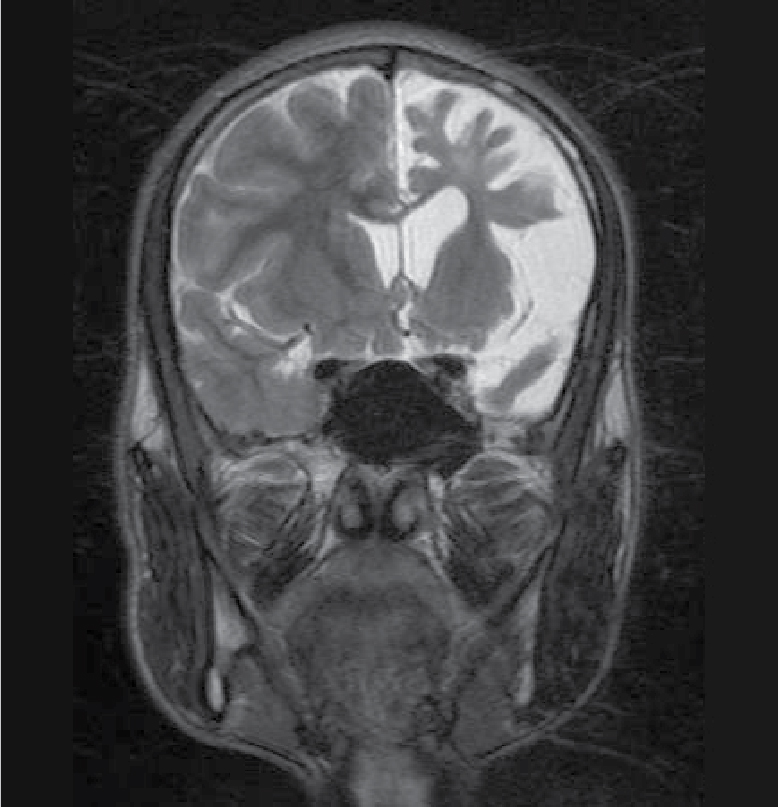

On examination, patient was conscious and oriented to time, place and person. There was extension at right elbow joint; pronated forearm and flexion at wrist joint (Fig. 1). Mental status examination revealed impaired calculation and Mini-Mental State Examination (MMSE) revealed a score of 24/30. On cranial nerve examination, patient had right upper motor neuron (UMN) type of facial nerve palsy. On motor examination, patient had gross wasting in right upper and lower limbs. Tone was markedly increased on right side of body with reduced power (3/5), brisk deep tendon reflexes and reduced sensation to touch, pain, temperature, vibration and proprioception. Plantar response was extensor on right side. Biochemistry was unremarkable. A provisional diagnosis of insidious onset gradually progressive sensorimotor hemiparesis with focal to generalized epilepsy with mental retardation was made. Noncontrast computed tomography (NCCT) head and magnetic resonance imaging (MRI) brain was performed, which revealed left cerebral hemiatrophy as evidenced by reduction in volume, prominence of cerebral sulci and dilation of left lateral ventricle. No other bony vault abnormality or prominence of frontal and mastoid air cells were seen (Figs. 2-4). Electroencephalogram (EEG) revealed epileptiform discharges in the form of sharp and slow wave complexes. Histopathology could not be done as attendants were not willing. Patient fulfilled the diagnostic criteria of RE (Table 1). He was treated with tablet phenytoin 100 mg TDS; tablet azathioprine 50 mg OD was started to halt progression of the disease. Patient had no episode of seizure thereafter. He was advised follow-up and repeat MRI brain was planned to check for any progression.

Figure 4. T2WI showing loss of volume of white matter in left cerebral hemisphere with thinning of gyri.